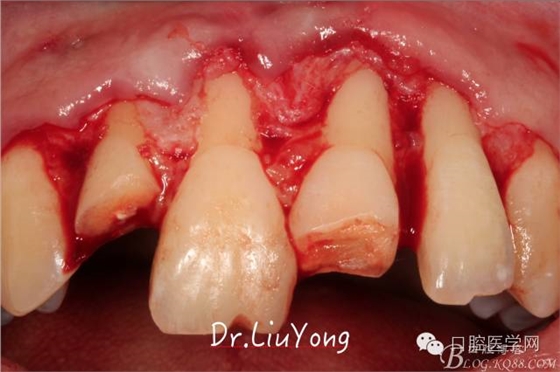

系帶手術(shù)后兩周,進(jìn)行上頜前牙唇側(cè)的牙齦退縮的手術(shù)治療,由于局部附著齦缺如及牙齦厚度不足,因此同期進(jìn)行上皮下結(jié)締組織移植,解決附著齦及牙齦厚度不足的問題。

術(shù)中,可見明顯的唇側(cè)骨開裂,如上圖: